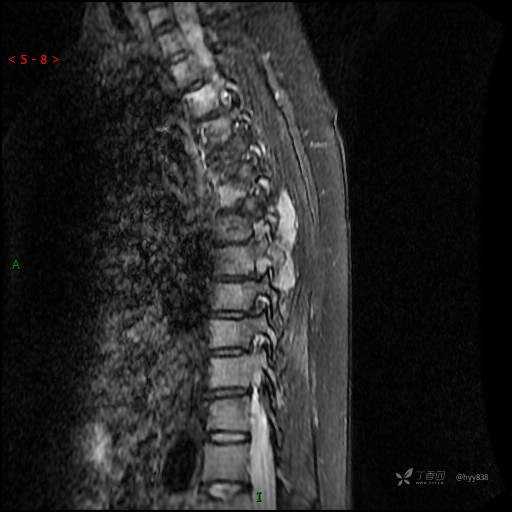

MRI SAG T2WI+T1WI